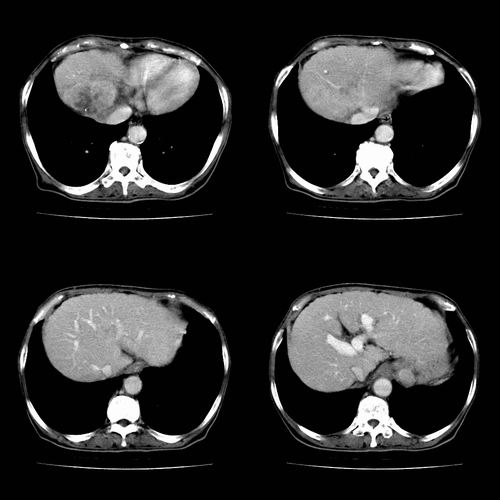

图片非常漂亮!肝内病灶符合较典型肝癌的强化方式,速升速降,其内可见坏死,腹膜后示肿大淋巴结融合成团,包绕腹主动脉、腹腔干动脉、肠系膜动脉。右肾小囊性病灶,未见明显强化。

诊断:肝癌并腹膜后淋巴结转移。

肝癌并腹膜后淋巴结转移。

根据增强的特点看,应该是肝癌,腹膜后胰头区低密度占位应该是腹膜后淋巴结增大,多考虑转移

肝癌伴腹膜后淋巴结转移。

支持肝癌并腹膜后淋巴结转移

肝癌并腹膜后淋巴结转移

1、肝右叶肝癌,后腹膜淋巴结转移(包绕腹腔干及肠系膜上动脉,推压门静脉、下腔静脉及胰头)

2、肝硬化、脾肿大

3、右肾小囊肿